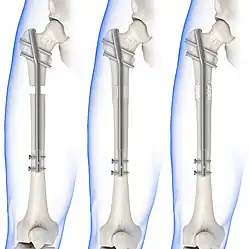

Internal fixators

Syndesmotic screws are the main, internal fixators used in surgeries for a Maisonneuve fracture. Two main types of syndesmotic screws are used: trans-syndesmotic screws (positioned at the level of the syndesmosis) and supra-syndesmotic screws (positioned above the syndesmosis).[15]

Based on several clinical results, syndesmotic screws are recommended to be fixed at least 1 centimetre proximal to the tibiofibular syndesmosis or 4 to 6 centimetres proximal to the tibiotalar joint line.[4][16] Cadaveric analyses, from a comparative study published in Foot & Ankle International in 1997, suggest that screw fixation at 2 centimetres proximal to the tibiotalar joint line is also adequate.[17] Biodegradable implants such as bioabsorbable screws, which do not require postoperative removal, may be used as an alternative to metallic hardware. However, biodegradable implants still limit rotation of the ankle and dorsiflexion of the foot.[4][6][13]